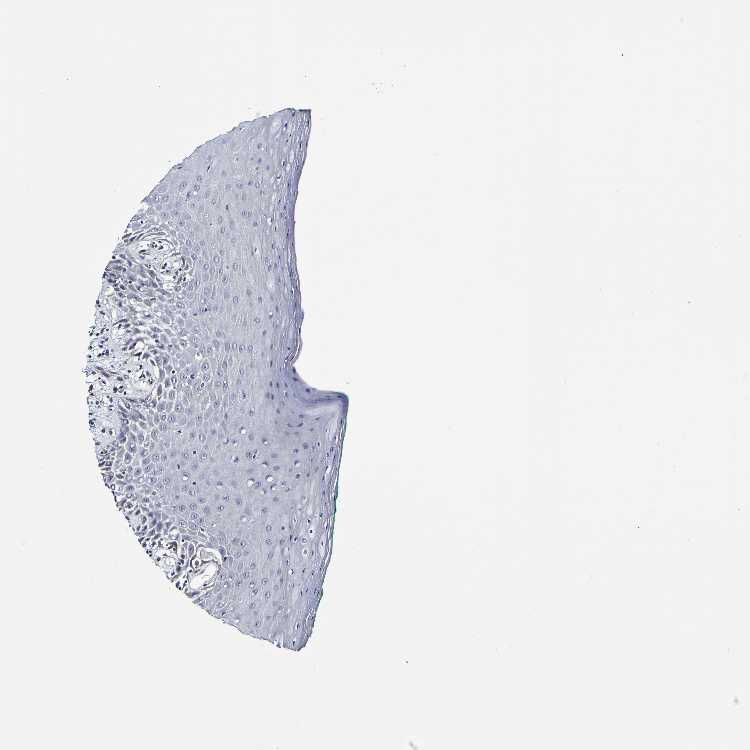

TISSUE PRIMARY DATA ORAL MUCOSA Show tissue menu

Oral mucosa

ORAL MUCOSA - Antibody stainingi

Antibody staining in the annotated cell types in the current human tissue is reported as not detected, low, medium, or high, based on conventional immunohistochemistry profiling in selected tissues. This score is based on the combination of the staining intensity and fraction of stained cells.

Each image is clickable and will lead to virtual microscopy that enables deeper exploration of all samples and also displays staining intensity scores, fraction scores and subcellular localization as well as patient and tissue information for each sample.

Antibody HPA044758Antibody CAB011582

Squamous epithelial cells LowNot detected